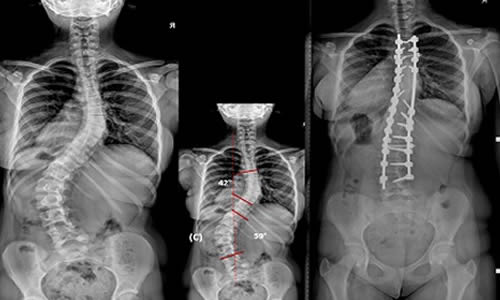

Adölesan İdiopatik Skolyoz tedavisinde korse tedavisinin yeri cerrahi tedavi yöntemlerinin gelişmesi ile azalmaktadır, ancak yine de uygun hastalarda tercih edilen bir tedavi yöntemidir. Korse tedavisi, oluşan eğriliği mekanik olarak temas noktalarından orta hatta iten ve aynı zamanda omurgaya (traksiyon) asılma gücünü uygulayan bir prensiple çalışır. Bu temas noktaları leğen kemiği, koltuk altı, göğüs kemiği (sternum) ve eğriliklerin en çıkıntılı yerleridir. Eğriliğin yerleşim yeri boyna yakınsa kafayı da içeren ilave temas noktaları eklenir.